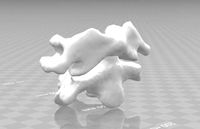

First cervical vertebra atlas

...del first cervical vertebra atlas for download as stl and obj on turbosquid: 3d models for games, architecture, videos. (1617259)